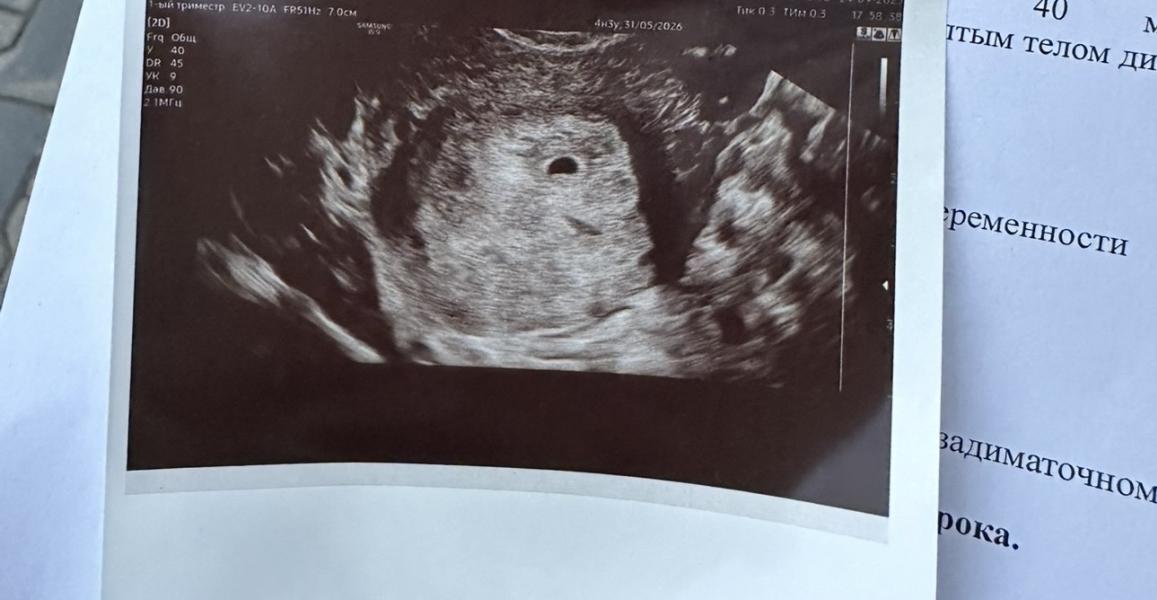

Привет всем! Сходила на узи на 4 день задержки, хгч тогда был 1617 (23.09)

Увидели в матке плодное яйцо 3,4 мм. Пока всё.

Я сегодня сдала хгч (28.09), получается через 5 дней после узи, результат - 6900